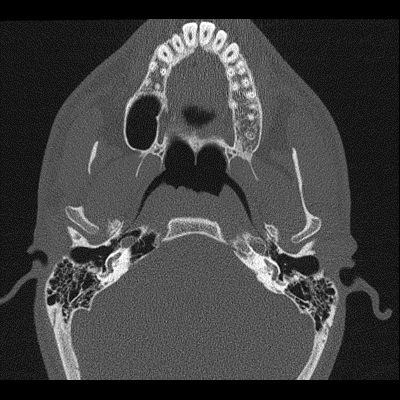

19 yaş, K

Kulakta dolgunluk, nefes sesini ve kendi sesini abartılı şekilde duyma

Tanınız nedir?